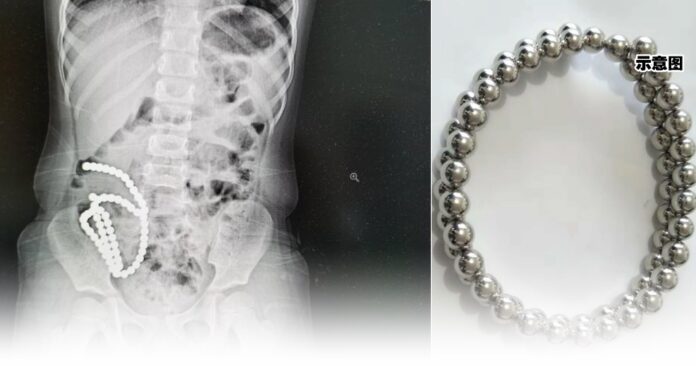

中国浙江一名4岁女童最近一个月反复腹痛,家人以为是普通的肠胃炎,直到情况加剧而在本月3日到当地医院就诊时,才通过CT检查发现,她肚子里有密密麻麻一长串珠子!

当天,医生为女童做了手术,由于磁力珠过多无法采用微创,她的腹部开了一个8公分的口子。医生一颗颗取出磁力珠,并对肠穿孔部位进行修补,手术进行了快3个小时才完成。

手术后,医生统计了一下,总共从女童肠道内取出61颗磁力珠,这一连串珠子造成了14处肠穿孔。